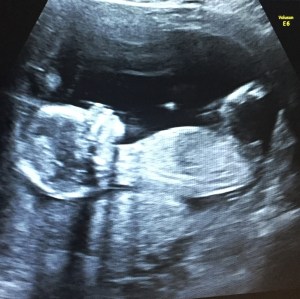

I made an appointment with my doctor’s office to tell them I’d had a positive pregnancy test and got a phone call with a ‘congratulations!’ and the address of the website where I could refer myself to the local hospital for maternity care. My first ultrasound was booked in for 12 weeks. That was the first time I saw any medical professional, and until I saw my little baby moving on the ultrasound screen and heard the woosh woosh of her heartbeat, there was still a part of me that thought I was imagining the whole thing.

My partner wasn’t allowed to come to any of my scans in the first or second trimester due to COVID restrictions. I was alone when I found out we were having a girl. I told my partner the news in the downstairs hallway, where we hugged beside our bikes and piles of shoes.

The hospital relaxed the rules a little during my third trimester, and he was able to see his daughter for the first time at 36 weeks. Until then, for eight months, the pregnancy had been just mine. My partner saw my body change, felt the baby moving, but it was all still a bit unreal for him. Until suddenly, with four weeks to go, there was our daughter yawning at us in black and white. Now he was a part of it too.